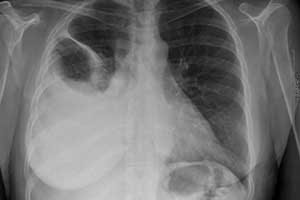

пневмония с плевритом

Здравствуйте! Мама лежит в больнице 1.5месяца (томография показала: двухсторонняя пневмония с плевритом) прокололи антибиотик 14 дней состояние ухудшается(одышка ,отеки ног,тахикардия, Аритмия}Врачи сказали пневмонию вылечили у неё запущенный бронхит и воспаление перешло на сердце.Возможно ли такое,что пневмонию вылечили ,а бронхит нет.